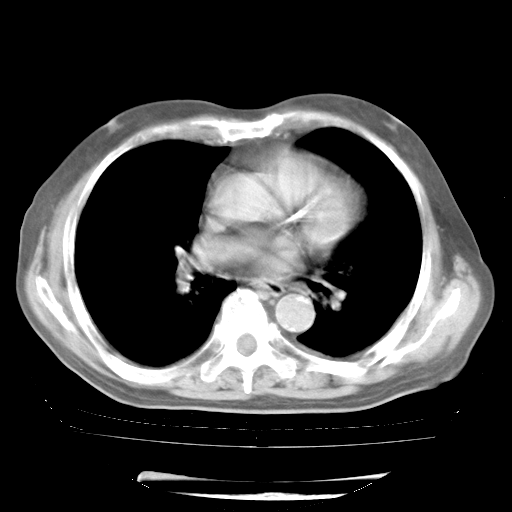

4月28日肺部CT——再次出现类似去年5月9日——透光度降低,“间质性”改变。

4月28日肺部CT——再次出现类似去年5月9日——磨玻璃样、间有“粟粒样”改变。

4月28日肺部CT